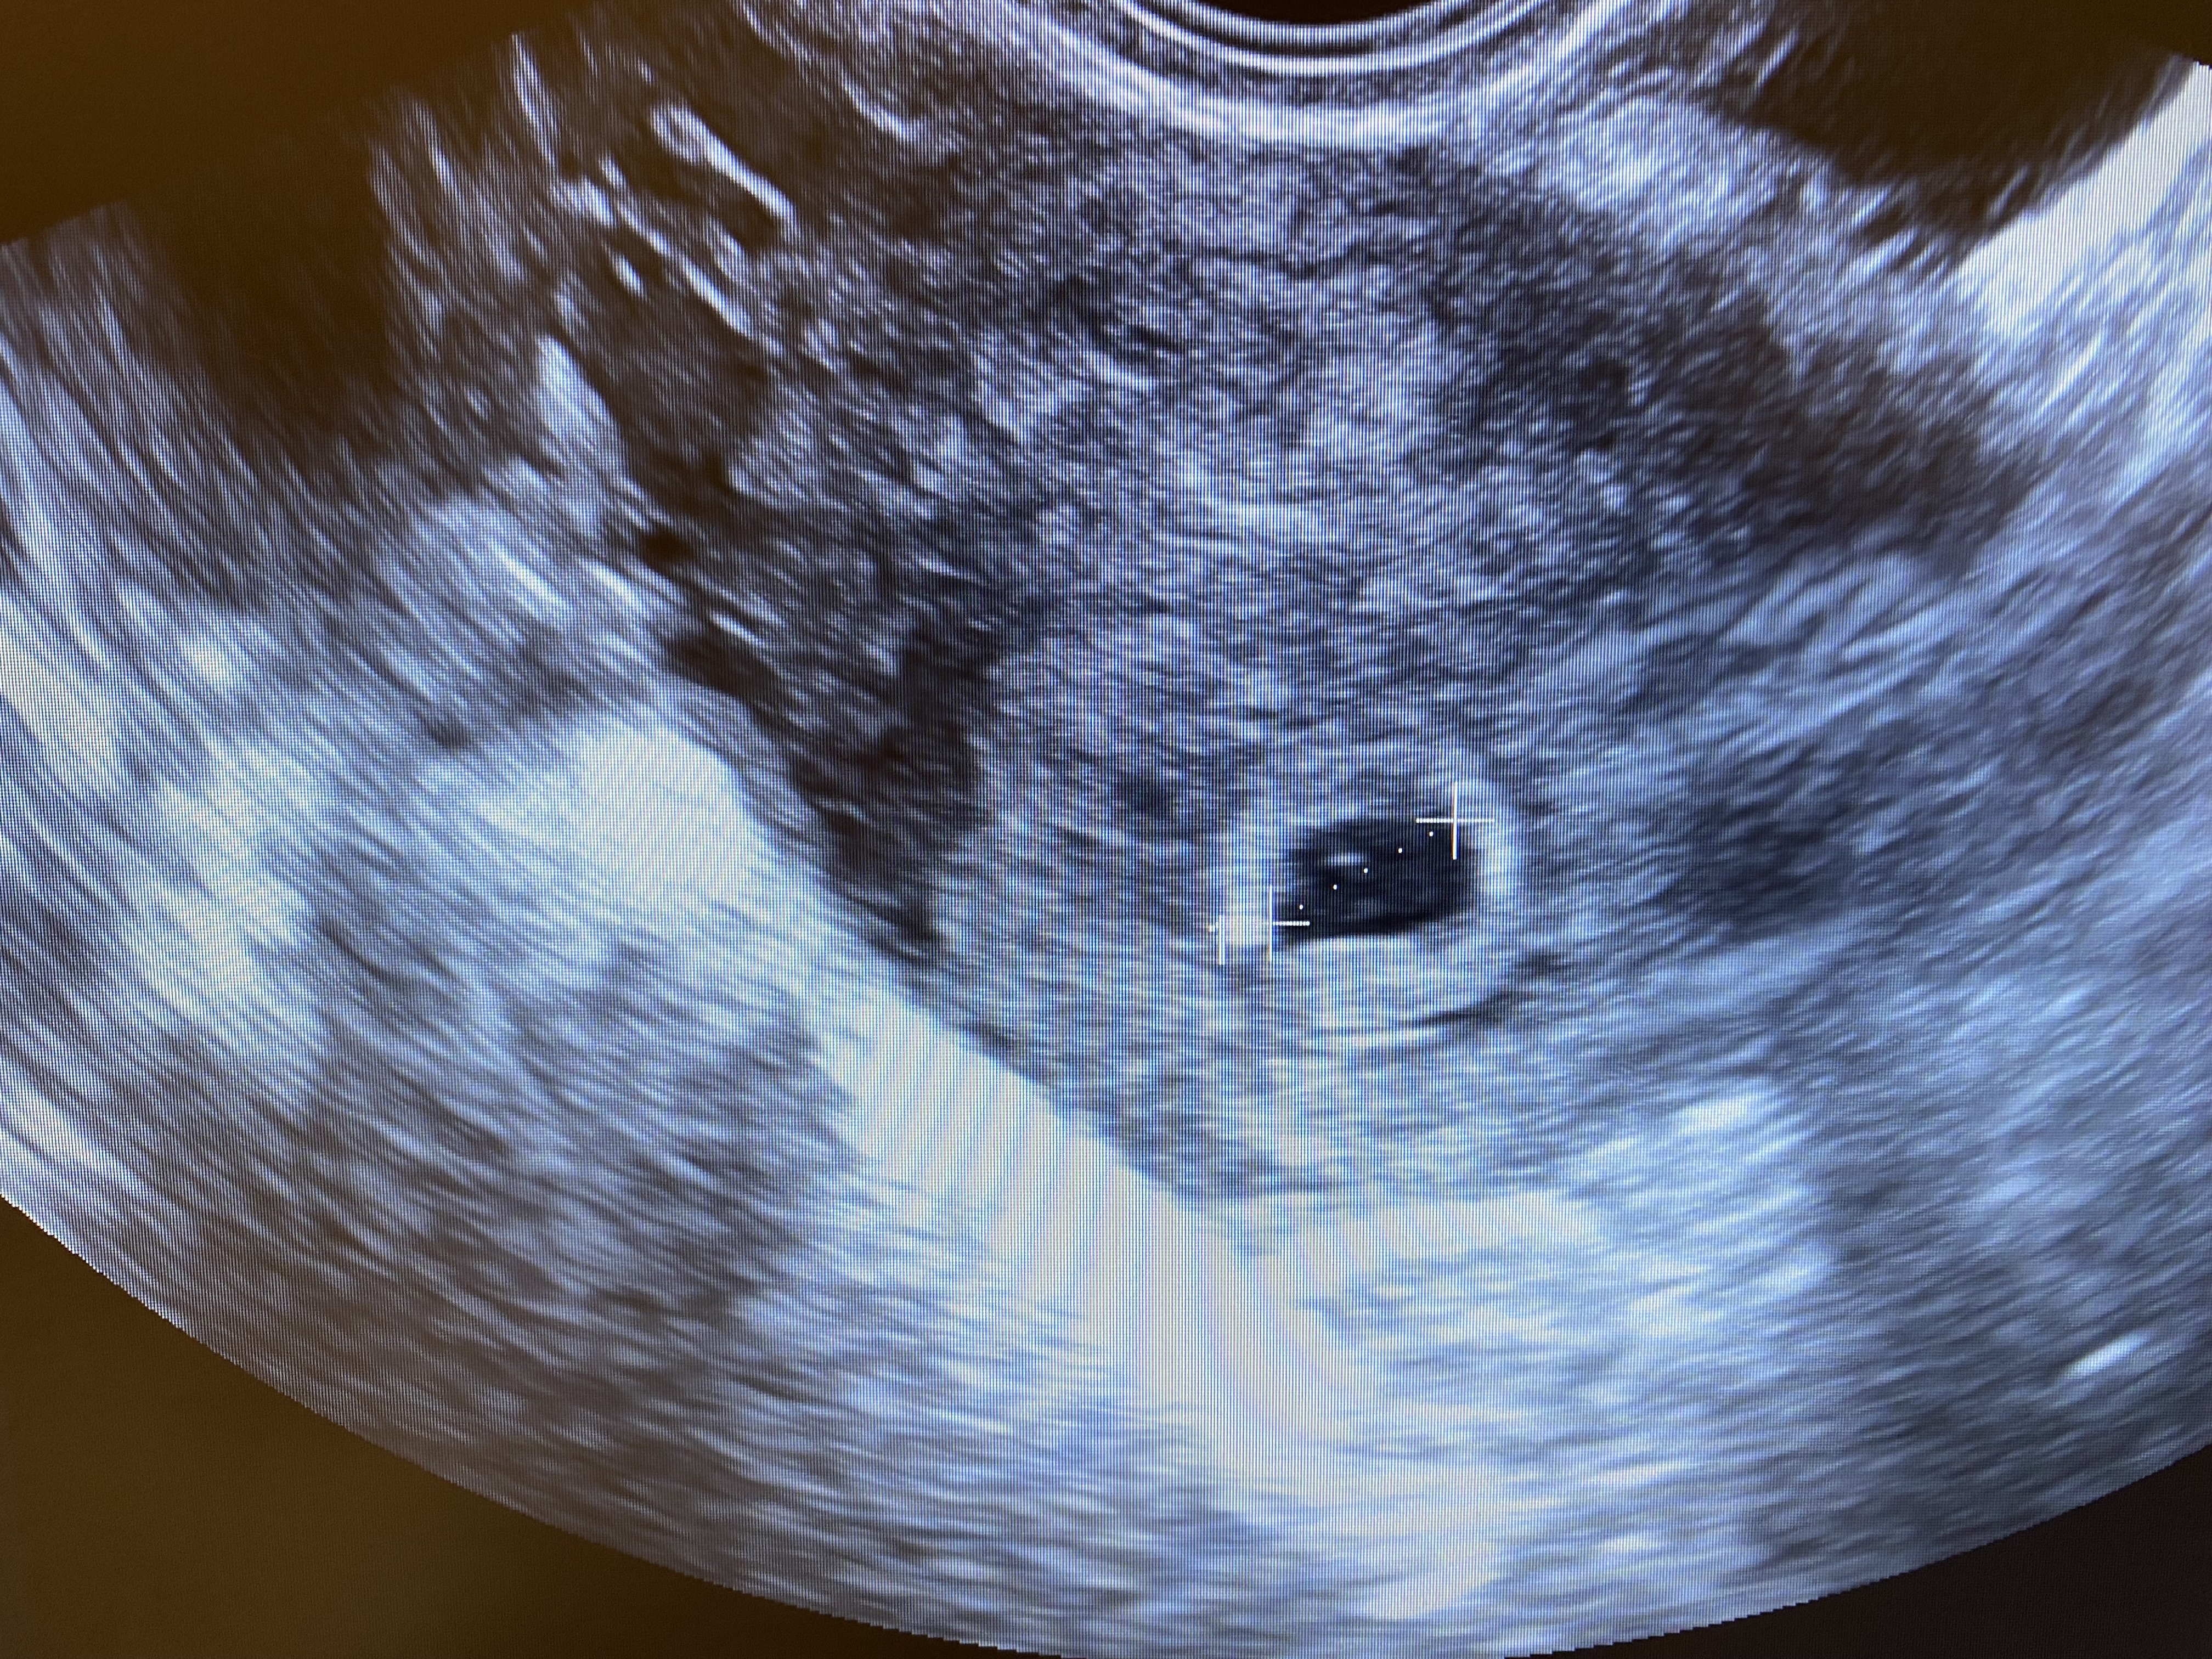

Первое УЗИ. Срок по узи 2-3 недели 🥹

Ксения, только СВД - 8мм

также было кстати, тоже сказали срок около 3 недель, плодное яйцо в матке, но эмбрион еще не лоцировался и тоже сказали повторно через 2-3 недели прийти. но так получилось, что следующее узи случилось уже через неделю и сердцебиение уже было) и срок сказали 6.3

Январька, это не магия,просто 2-3 недели это не акушерский срок,мне тоже на первом УЗИ (22 дпо)пя 8 мм,жм 1,6 в заключении 3 недели, акушерских 5,1,ну логично что 3 недели это от зачатия,а это и есть 5 акушерских,у меня и было 22 дпо т.е 3 недели от овуляции,через 9 дней на 31 дпо по узи эмбрион и сб и 6,2 недели по ктр,просто на первом УЗИ поставили срок от зачатия,а на втором уже акушерский по размеру эмбриона,а они отличаются на 2 недели,если вам пя нашли то срок 5 недель есть,3 недели акушерских это 21 д.ц беременности ещё нет,а 3 от зачатия это 5 акушерских

УЗИ на раннем сроке Плодное яйцо